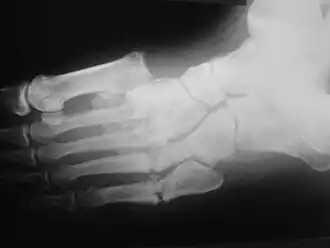

Radiografia do pé de homem de 45 anos mostra luxação divergente de Lisfranc do primeiro metatarsal, com fraturas metatársicas menores associadas.

A apresentação clínica varia dependendo do estágio da doença, começa com um edema leve e evolui a um inchaço e deformidade cada vez maiores. Inflamação, eritema, dor e aumento da temperatura da pele (3-7 graus Celsius) ao redor da articulação podem ser perceptíveis ao exame físico. Raios-X podem revelar reabsorção óssea e alterações degenerativas na articulação. Esses achados na presença de pele íntegra e perda de sensibilidade tátil protetora servem para diagnósticos da artropatia de Charcot aguda.